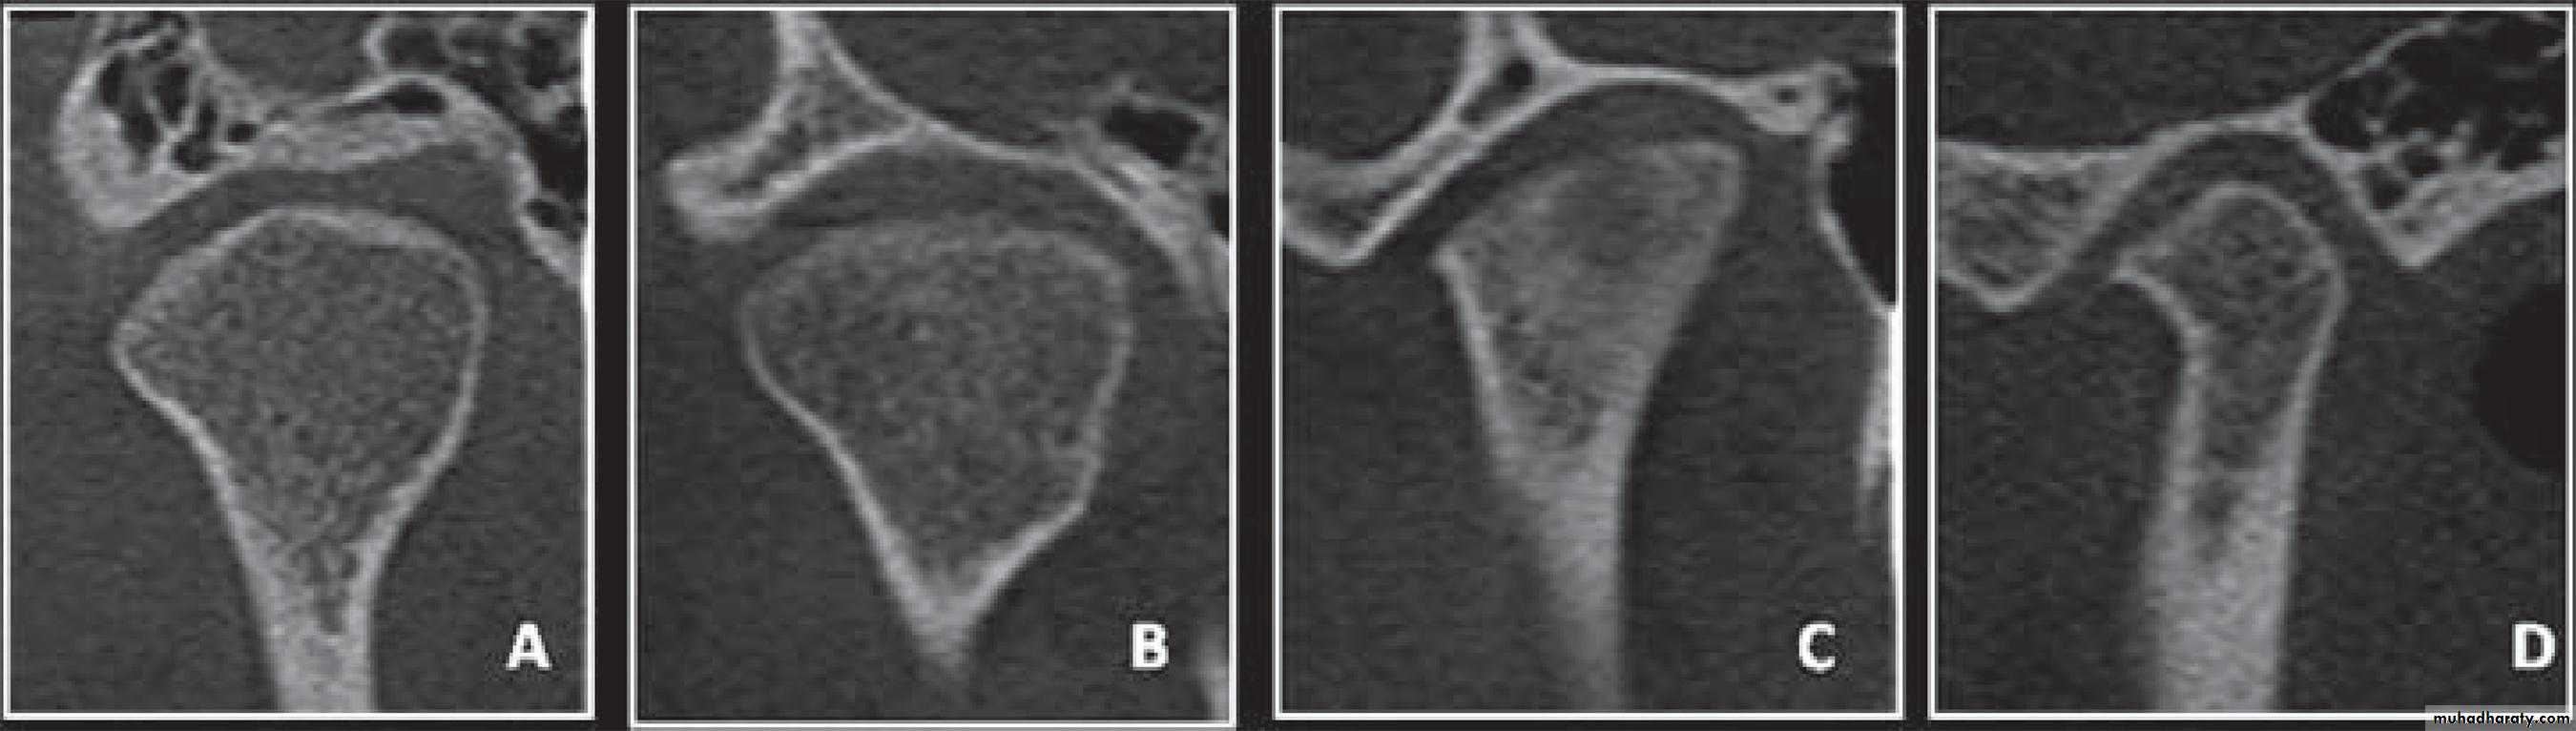

Cone-beam computed tomography images of temporomandibular joint showing morphological variation of the mandibular condyle. A- Normal (coronal view); B- Flattening (coronal view); C- Erosion (coronal view); and, D- Osteophyte (sagittal view)

Radiology

50Cone-beam computed tomography images of temporomandibular joint showing morphological variation of the mandibular condyle. A- Normal (coronal view); B- Flattening (coronal view); C- Erosion (coronal view); and, D- Osteophyte (sagittal view)